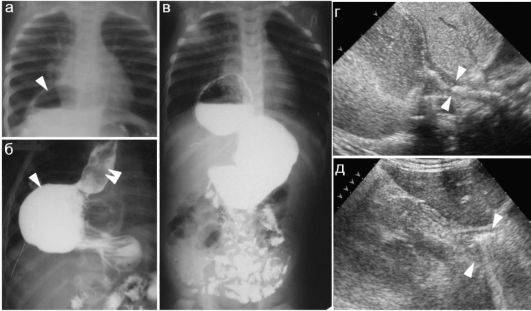

Обратитесь к врачу для точной диагностики. Если вы подозреваете наличие скользящей или плавающей грыжи пищевода, важно пройти медицинское обследование. Врач может назначить эндоскопию или рентген, чтобы подтвердить диагноз и определить степень заболевания.